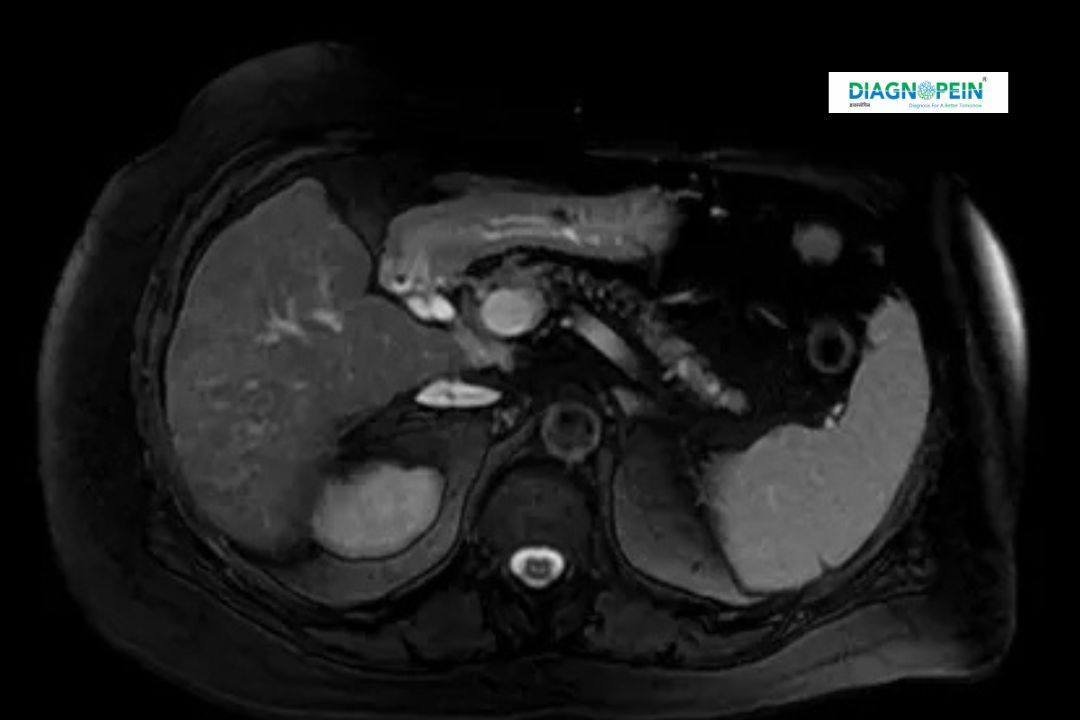

MRI Abdomen – Without Contrast is a diagnostic imaging test used to capture detailed pictures of the abdomen using magnetic resonance imaging technology. Unlike contrast studies, this scan does not involve the injection of contrast dye, making it ideal for patients who are allergic or sensitive to contrast agents.

At Diagnopein Nanded, this test uses modern MRI scanners to produce high-resolution images of internal organs such as the liver, kidneys, spleen, pancreas, gallbladder, and intestines. It helps identify abnormalities, diseases, and injuries with great accuracy and detail.

An MRI Abdomen – Without Contrast scan can evaluate:

1. Liver: Fatty liver, cysts, or tumors.

2. Kidneys: Stones, cysts, or structural changes.

3. Pancreas: Inflammation or masses.

4. Spleen: Size and texture evaluation.

5. Gallbladder: Stones and wall thickening.

6. Abdominal vessels: Blood flow and vascular health.